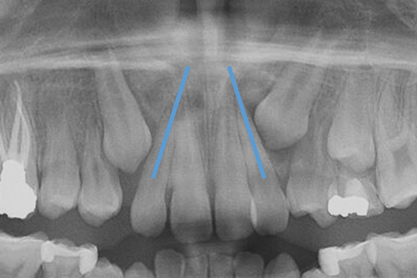

Fig 3. Impacted canine, dentofacial signs.

Figure 3

Fig 4. Impacted canine, radiographic signs. Lateral incisor crown distal flaring is apparent.

Figure 4

Dental impactions may occur for several reasons. A common occurrence is insufficient arch length leading to crowding. Another potential reason is early loss of primary teeth without proper space maintenance, allowing the permanent dentition to drift mesially and block out the primary tooth's successor. Maxillary canines are the most commonly impacted teeth besides third molars. These teeth have the longest path of eruption, are one of the last teeth to erupt into the mouth, easily become blocked out due to crowding or trauma history, and have a genetic component to being palatally impacted.5,6 Early signs of canine impaction may be severe crowding and the permanent lateral incisor crowns flaring distally. The crown of the impacted canine, in essence, is applying pressure to the roots of the lateral incisors in these instances (Figure 3 and Figure 4).

To prevent dental impactions, space maintenance and increasing the arch length are crucial factors. Literature shows that the extraction of primary canines often self-resolves about 90% of canine impactions as long as the canine crown is not mesial to the incisors, as per review of a panoramic image.7 Rapid palatal expansion (RPE) therapy is another approach to gain room and arch length.8